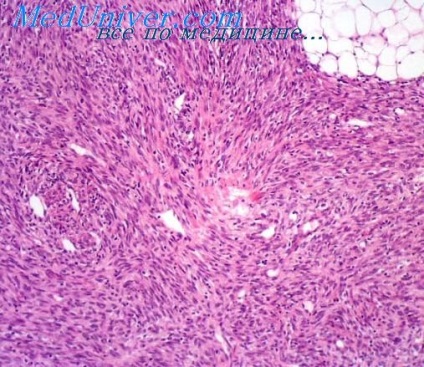

Változatos pleiomorf malignus fibrózus hisztiocitóma haraterzuetsya diffúz felhalmozódása véletlenszerűen elrendezett sejtek két típusa: orsó alakú sejtek jeleivel fibroblaszt és epitheloid köbös sejtek emlékeztető histiocyták. A második sejt fajta jellemzi, mint a jelenléte atípusos óriássejtek, többmagos, elosztjuk, a bizarr, beleértve három pólusú, mitotikus figurák. Amellett, hogy több hiperkromatikus magok ezek a sejtek is tartalmazhat a citoplazmában kis csepp zsírt, így ez egy habos megjelenése. Stroma tumorok általában nem fejeződnek, helyébe a tumor komponens. Azonban alapos tanulmány megtalálható között helyezkedik el a sejteket enyhe kollagén rostok, valamint különböző mennyiségű nyálka. is limfociták, plazma sejtek találhatók a tumorszövetben, eozinofil, neutrofil, ezek a sejtek néha összegyűlő véredények körül.

Óriássejtes fajok malignus fibrózus hisztiocitóma (syn. Malignus óriássejtes tumor a lágy szövetek) áll ugyanabban a sejt típusban, mint az előző változatban, de a jelenléte óriás oszteoklaszt sejttípus. Ezek a sejtek bőséges eozinofil citoplazmában több azonos kis magok és tartalmazhatnak zsírt vakuolumok és hemosziderin. Eltérően más típusú rosszindulatú rostos hisztiocitóma, sejtek vannak csoportosítva csomópontok körül sűrű szálas rostok tartalmazó edények. A csomópontok gyakori vérzés, nekrózis, képződése fokális osteoid vagy érett csont. Osteoid és a csont hajlamos arra, hogy lokalizálódik a periférián a helyén együtt orsó alakú sejtek. Az oszteoklaszt-típusú óriás sejtek, másrészt, koncentrálódnak a közepén a tumor és a kapcsolódó histiocyták.